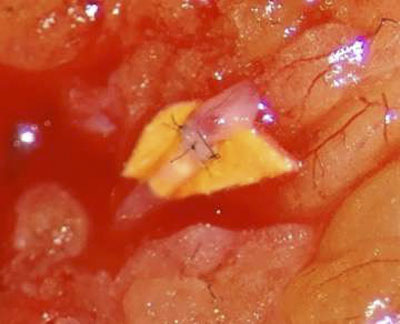

周涛、尚文博在高倍显微镜下行淋巴管-静脉吻合术

术中吻合